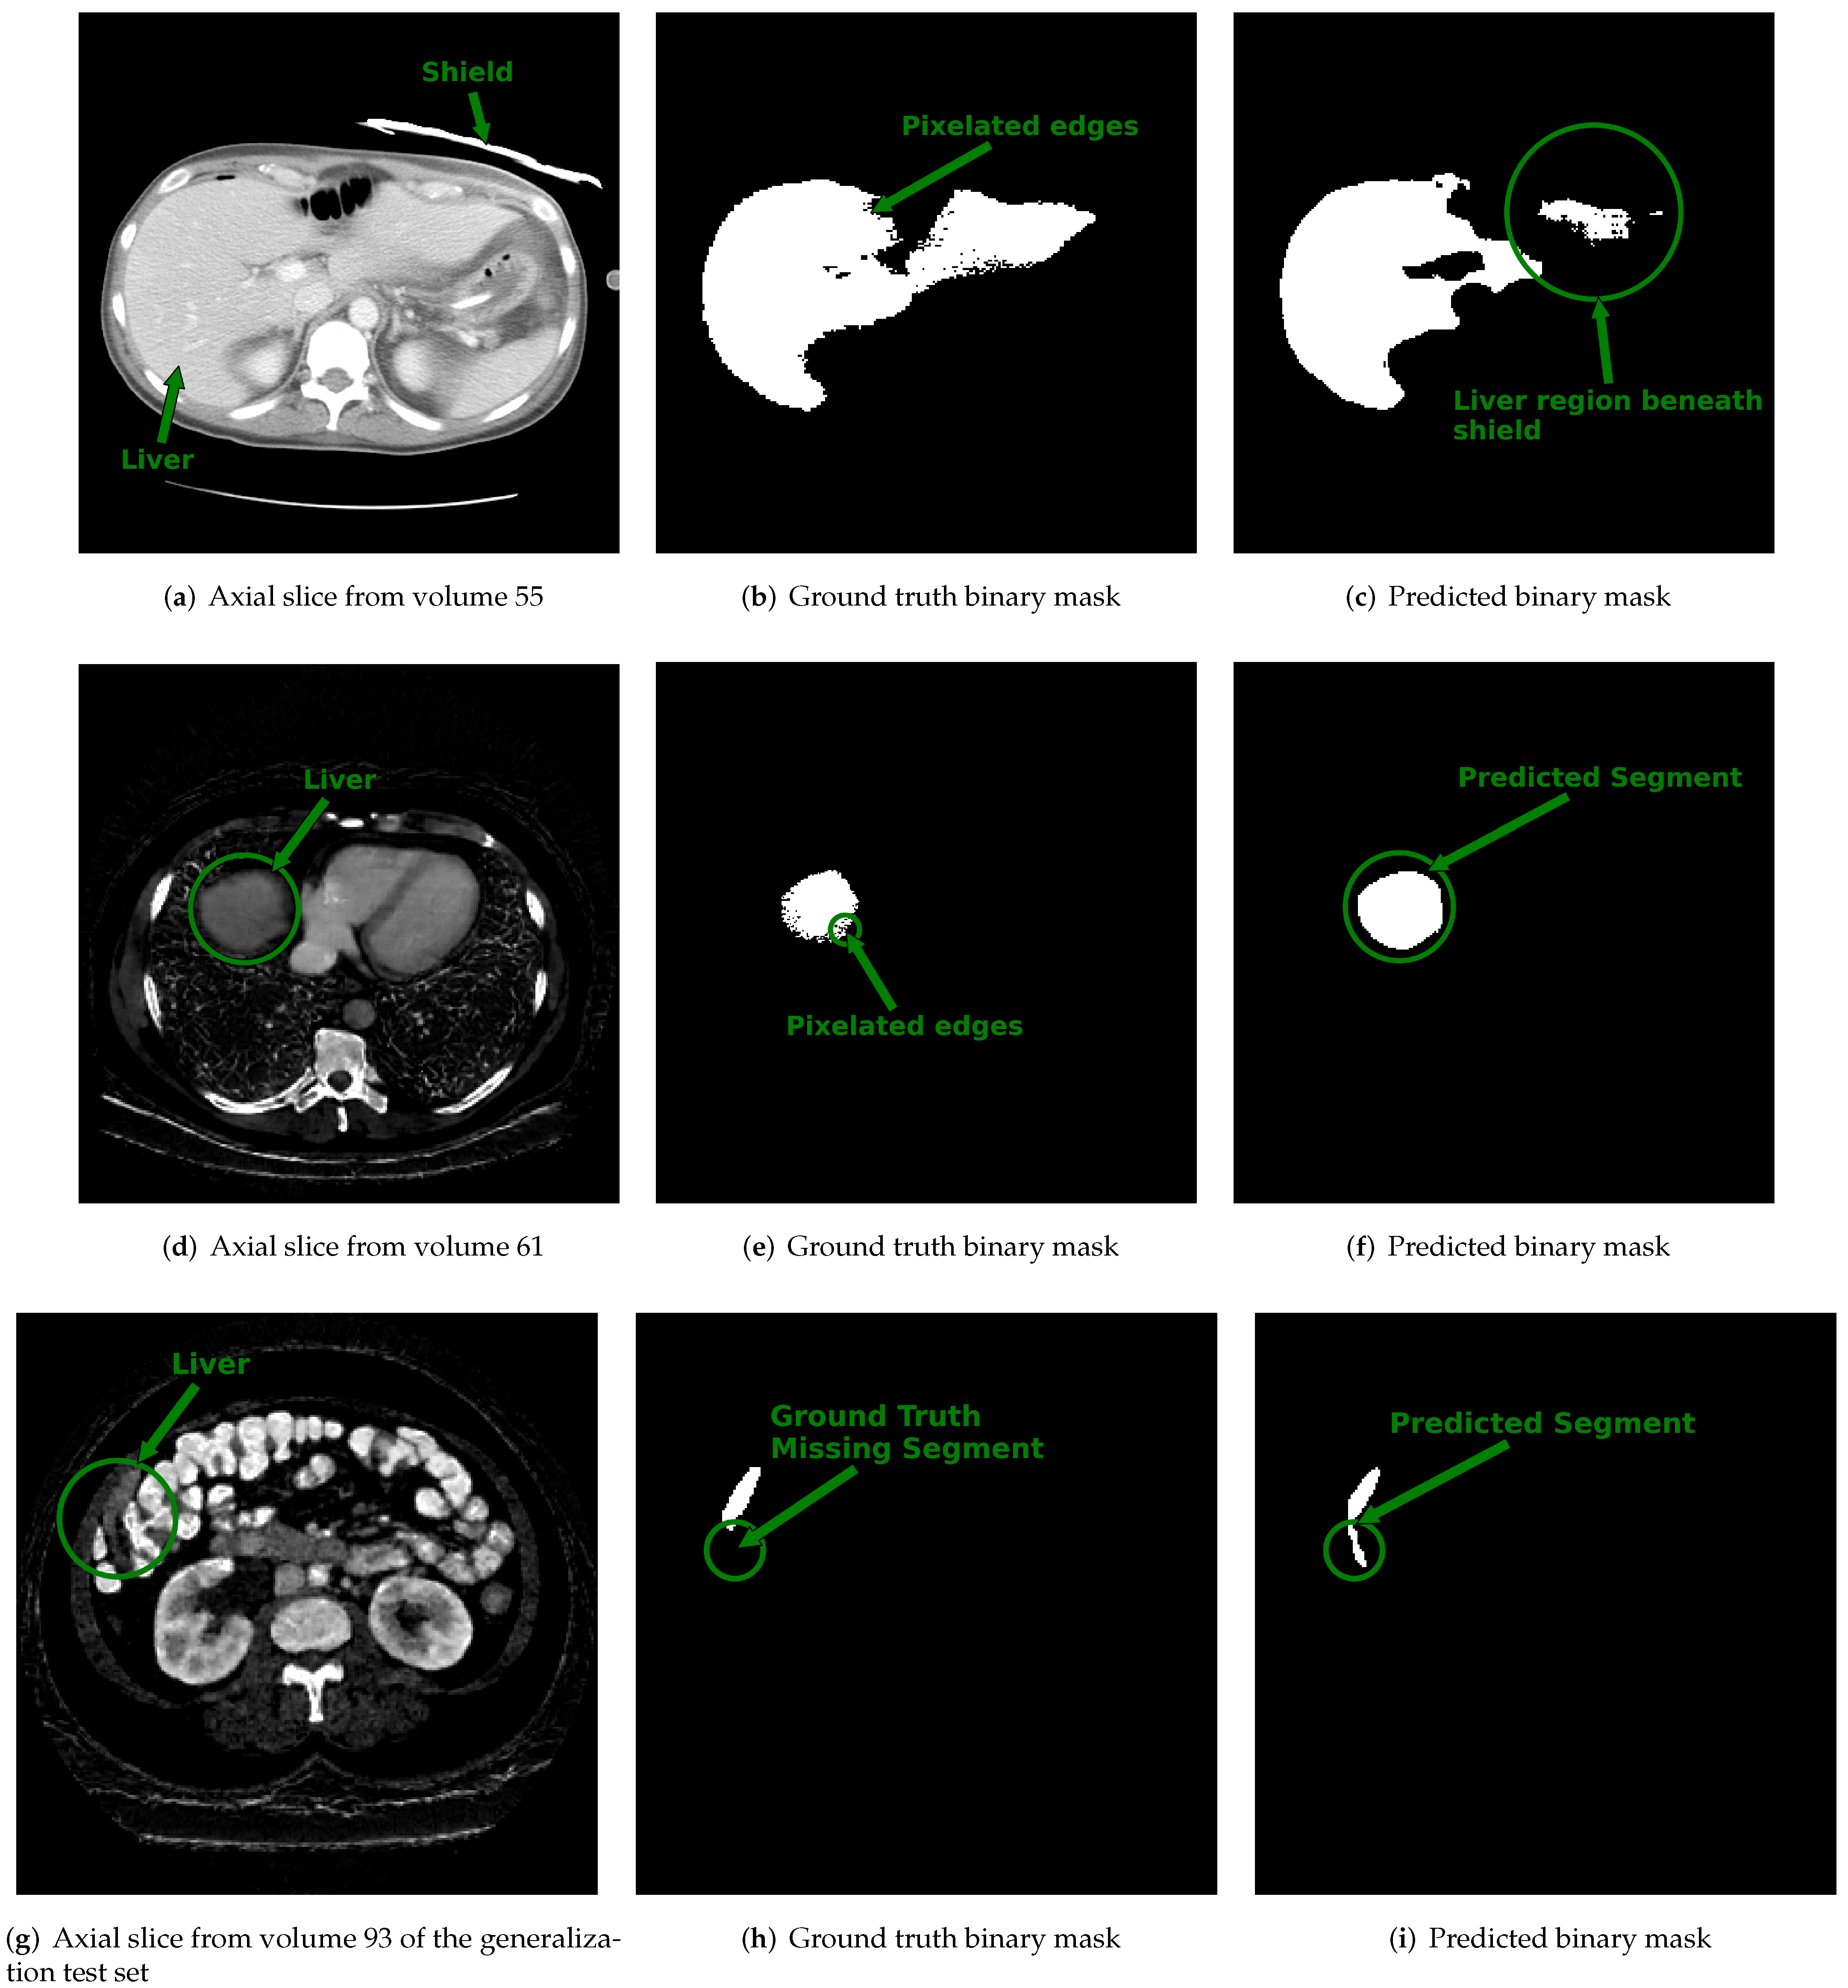

Examples of slices from scans within the dataset with the lowest DSC values (i.e., DSC < 0.8) are displayed in Figure 6. Figure 6a shows the center slice of the liver, which is where the liver occupies around 50% or more of the abdominal space. In contrast, at the start and end slices, the liver tissue occupies a minor proportion of the abdominal area, as illustrated in Figure 6d,g. We suspect that the reduced DSC scores at the start and end slice locations are a byproduct of the small size of the liver tissue relative to the background and partial volume averaging artifacts that falsely reduce or increase the pixel intensity value of border pixels. Consequently, the class imbalance and artifacts at the margins of the scan may increase the likelihood of misclassifying pixels.

Additional factors that contributed to the lower DSC score are also illustrated in Figure 6. In Figure 6a, we found a case in which a bismuth or lead shield was placed over the patient’s abdomen during the scan. The shield attenuates X-rays, causing beam hardening and streak artifacts, as well as increasing noise in the organs beneath it. In addition to the shield, the ground truth annotation provided by the dataset organizers shown in Figure 6b contained pixelated edges. As shown in Figure 6c, the combined effect caused the 3D u-net to undersegment the portion of the liver directly under the shield. Figure 6d–f show an example slice with its ground truth contour that contains pixelated edges and the predicted output of the 3D u-net. In this case, the reduced DSC score was not a result of over or under segmentation by the 3D u-net but was, instead, due to the differences arising from the pixelation in the ground truth and lack thereof in the predicted output. In another example shown in the final row of Figure 6g–i, the reduced DSC score for this case was because the ground truth annotation displayed in Figure 6h did not outline the entire segment of the liver. However, as illustrated in Figure 6i, the predicted output of the 3D u-net included the full extent of the liver. Several scans in the CT-ORG dataset had ground truth annotations that were rough outlines of the liver or consisted of pixelated edges [45]. Despite imprecise ground truth contours, the 3D u-net trained using synth-DECT MDI scans was still able to predict the complete extent of the liver tissue for many patient scans.

Figure 6. Displayed are example cross sectional axial slices with ground truth annotations and predicted contours from 3D u-net. Top Row: (a) Axial slice from single energy CT (SECT) scan of a patient within the CT-ORG training dataset shows an attenuating shield placed over segment 2 of the liver. (b) The ground truth binary image provided for the slice shown in (a) has pixelated edges pointed to by the arrow. (c) The output predicted by the 3D u-net for the slice in (a). The circled region pointed to by the arrow shows the area under the shield where the 3D u-net under-segmented the liver. Middle Row: (d) The synthetic dual-energy CT (synth-DECT) material density iodine (MDI) slice from a patient in the held-out test set. The liver is circled and pointed to by an arrow. (e) The ground truth binary image provided with the CT-ORG dataset for the slice shown in (d) also has pixelated edges that are circled and pointed to by the arrow. (f) The output predicted by the 3D u-net is circled and pointed to by the arrow. It incorporated the entire extent of the liver, without any pixelation. Bottom Row: (g) An axial slice from a patient scan in the generalization test set. The circled area and arrow point the portion of the liver at the margins of the liver. (h) The ground truth slice for the image shown in (g) does not contain a portion of the liver. The circle and arrow point to the segment of the liver missing from the ground truth annotation. (i) The predicted output by the 3D u-net. The circle and arrow point to the segment of the liver that was successfully identified by the 3D u-net, but was missing from the ground truth annotation shown in (h). The top row shows the impact of noise and beam hardening arising from the shield’s on the predictions of the 3D u-net. Several scans in the training dataset had ground truth contours with pixelated edges, missing segments of the liver, or inclusion of non-liver tissue, as shown in this figure.